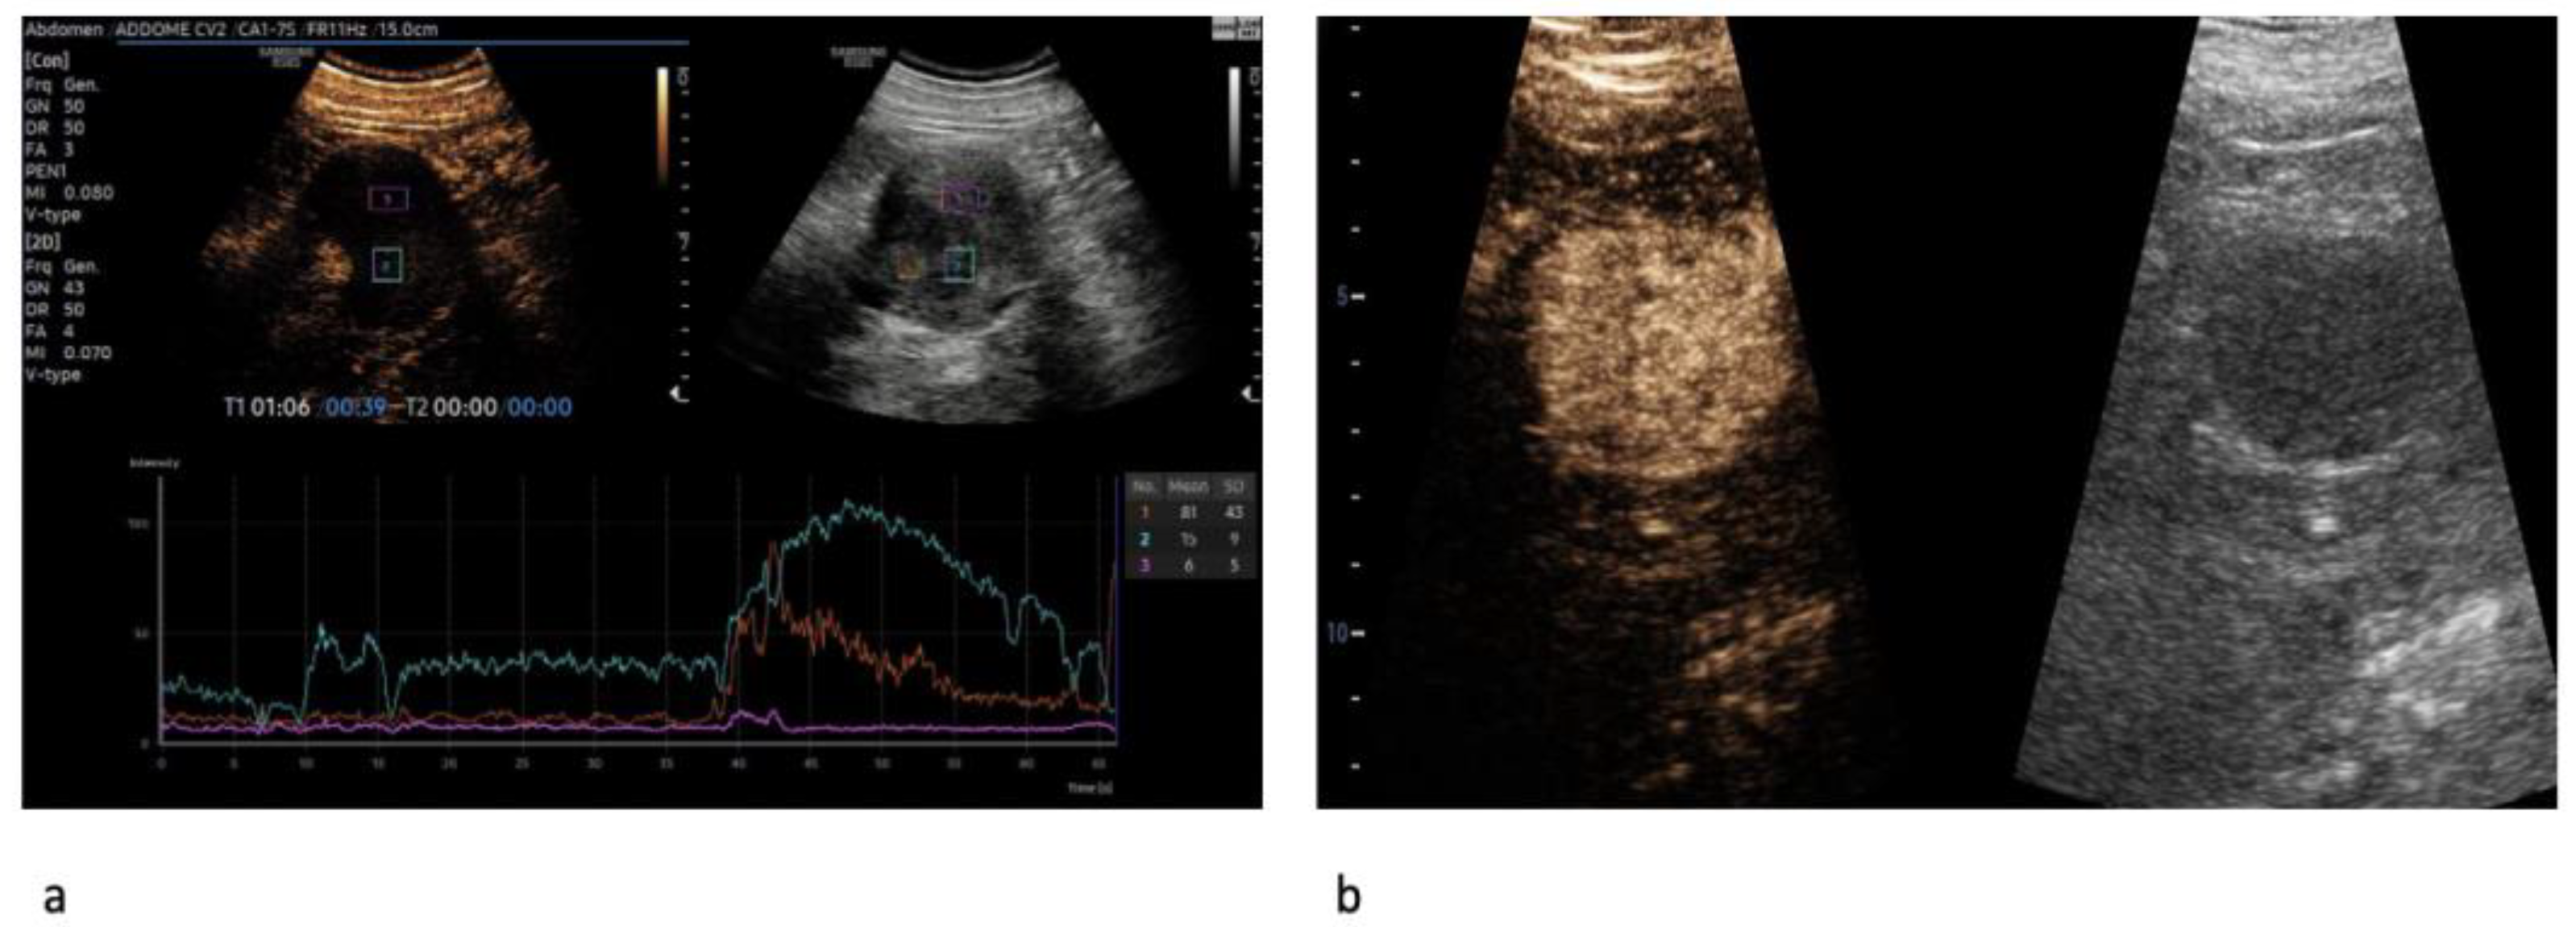

| Wash-in | ||||

| Fast | 95 (75.4%) | 83 (80.6%) | 12 (52.2%) | 0.004 |

| Synchronous/Slow | 31 (24.6%) | 20 (19.4%) | 11 (47.8%) | |

| Enhancement | ||||

| Homogeneous | 48 (38.1%) | 27 (26.2%) | 21 (91.3%) | <0.001 |

| Heterogeneous | 78 (61.9%) | 76 (73.8%) | 2 (8.7%) | |

| Wash-out | ||||

| Fast | 55 (43.7%) | 52 (50.5%) | 3 (13.0%) | 0.001 |

| Synchronous/Slow | 71 (56.3%) | 51 (49.5%) | 20 (87.0%) | |

| Rim-like enhancement | ||||

| No | 30 (23.8%) | 15 (14.6%) | 15 (65.2%) | |

| Yes | 96 (76.2%) | 88 (85.4%) | 8 (34.8%) | <0.001 |